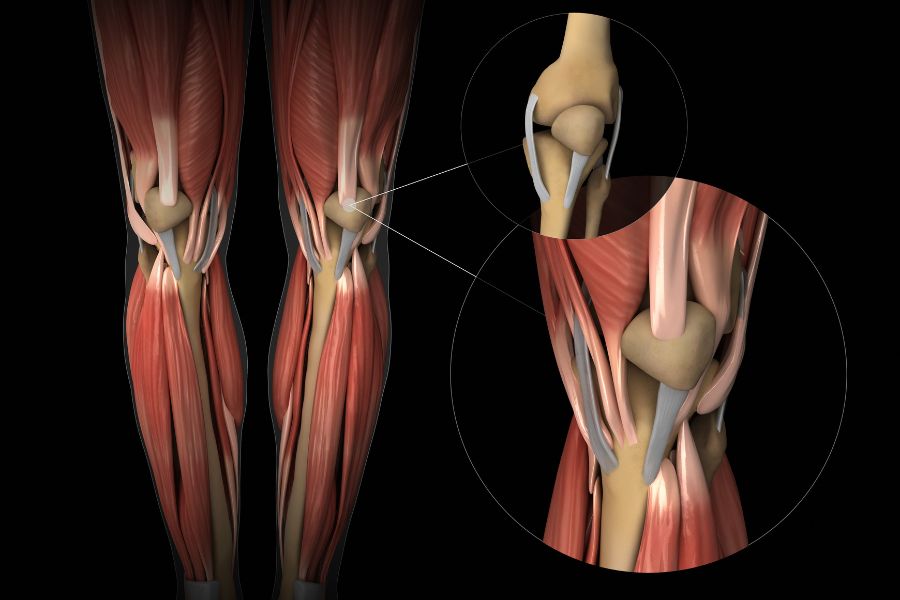

Doç. Dr. Tunay Erden, spor yaralanmaları ve protez cerrahisi alanlarında uzmanlaşmış ortopedi ve travmatoloji cerrahıdır. Özellikle ön çapraz bağ (ÖÇB/ACL) ve arka çapraz bağ (AÇB/PCL) rekonstrüksiyonu, menisküs yırtıkları, kıkırdak hasarı, çoklu bağ yaralanmaları ve kompleks diz cerrahisi konularında ileri düzey deneyime sahiptir.

• Spor ve Diz Yaralanmaları

Sporcularda sık görülen yaralanmaların (menisküs yırtıkları, ön ve arka çapraz bağ (ACL) yaralanmaları, iç ve dış yan bağ yaralanmaları, kas ve tendon) tanı ve tedavisini en güncel bilgi ve yöntemlerle gerçekleştiriyoruz